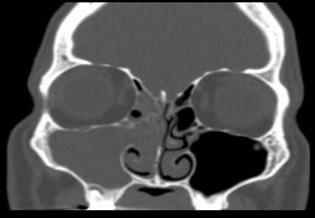

Las proyecciones que se suelen solicitar son la mentonasoplaca de Waters y el perfilograma (radiografía simple de huesos propios de la nariz)

Figura 35. Fractura nasal, nótese la deformidad, tumefacción y epistaxis. Figura 36. Radiografías (Rx) en fractura nasal. Rx izquierda (perfilograma) y Rx derecha (proyección de Waters)